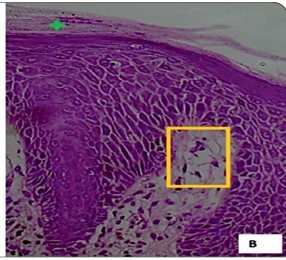

Wolf’s isotopic response refers to the occurrence of a new dermatosis at the site of a previously healed and unrelated skin condition. While commonly associated with viral triggers such as herpes simplex or zoster, non-viral initiators are rarely reported. We present two unique cases of psoriasis developing exclusively at sites of old scars from non-viral causes. The first case involved a 33-year-old male who developed a psoriatic plaque over a thermal burn scar on the dorsum of the hand. The second case featured a 28-year-old male with psoriatic lesions localized to an atrophic scar following a traumatic injury to the shin. Both cases lacked involvement of other body areas. Diagnosis was confirmed by clinical features, dermoscopy, and histopathology. These cases highlight an atypical presentation of Wolf’s isotopic phenomenon and underscore the potential role of localized immune dysregulation and scar-mediated vulnerability in the development of secondary dermatoses.